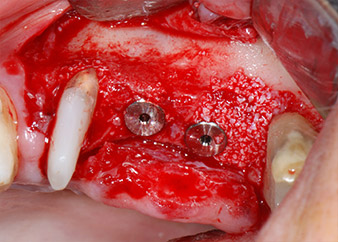

The implants (Restore, Keystone Dental, diameter 3,75 mm, length 8.0 mm) were placed with the implant motor (Figs. 11 and 12).